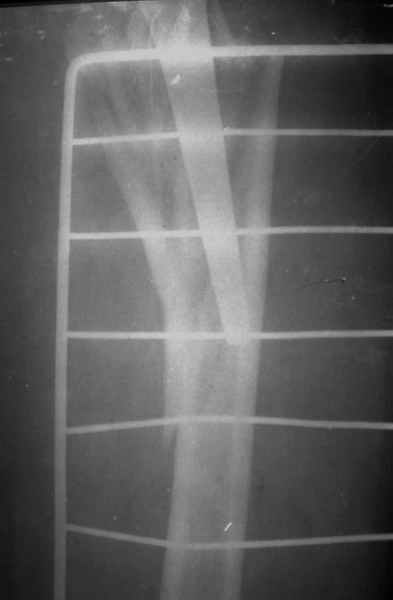

По Ванкуверовской классификации это 2А тип перипротезного перелома на фоне нестабильности ножки эндопротеза и остеолиза проксимального отдела бедра. Решение - удаление предыдущей ножки, имплантация ножки дистальной фиксации. Канал виден на ограниченном участке, исходя из увиденного, я бы предпочел цилиндрическую ножку 200 мм полнопокрытую. Фрагменты собрал бы вокруг ножки серкляжами. Если будут мелкие фрагменты, то есть смысл взять кортикальные аллографты и поджать фрагменты по типу вязанки хвороста. Отношение к чипсам двоякое - на любителя, главное - надежная дистальная фиксация ножки, обеспечивающая первичную стабильность. Что-то похожее мы оперировали несколько лет назад, качество первичных Р-грамм оставляет желать лучшего, но суть понятна. Результаты через 3 года.

С уважением, Р.Тихилов